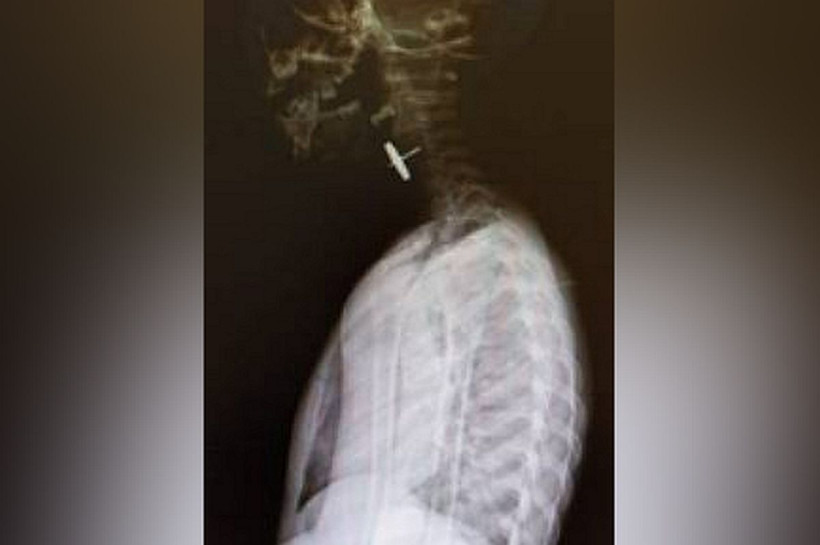

Фото: minzdrav.amurobl.ruКолесико от машины застряло в верхней трети пищевода мальчика. Из-за тяжести возможных осложнений ребенок нуждался в срочной транспортировке в больницу более высокого уровня. С помощью спецавтотранспорта в условиях снегопада и плохой видимости ребенка за пять часов доставили в медучреждение. Врач — анестезиолог-реаниматолог и медицинская сестра-анестезистка проводили мониторинг витальных функций, подавали увлажненный кислород и продолжали необходимую терапию.

— Инородное тело, застрявшее в пищеводе, представляло собой металлическую конструкцию на штыре до 1,5 сантиметра в длину с маятником округлой формы до 1,5 сантиметра в диаметре. Инородные тела такой сложной конфигурации опасны перфорацией органов, тканей и сосудов с дальнейшим развитием кровотечения и перитонита и требуют квалифицированной хирургической помощи, — пояснил Петр Ширяев.